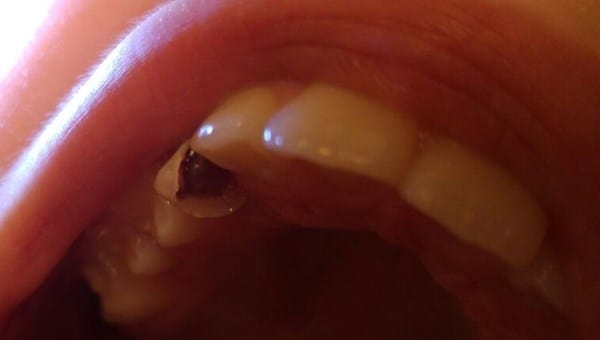

Mi hija lleva ya unos cuantos meses con un colmillo de leche colgando. Justo debajo de él, ya se le ve el definitivo. Vamos, que está para darle un tironcito. El problema es que hoy se le ha girado y he visto que lo que realmente le une a la encía (o eso parece), es algo morado muy oscuro como un trozo de encía o un coágulo de sangre. La verdad es que impresiona un poco, y no sé que es. Estoy preocupada. Al moverlo ella misma dice que le duele. ¿Qué hago?